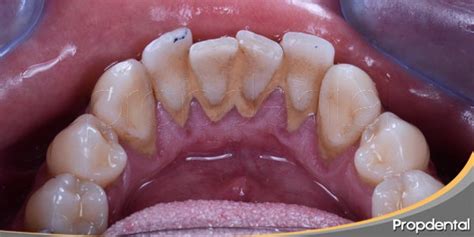

El depósito sobre los dientes que se conoce como sarro o cálculo dental se forma mediante la mineralización de la placa bacteriana. Inicialmente, tras el consumo de alimentos y la falta de higiene, se acumula placa blanda compuesta de bacterias, restos orgánicos y sales de la saliva (placa bacteriana). Si esa placa no se remueve regularmente, en cuestión de días comienza a calcificarse: los iones de calcio y fosfato presentes en la saliva precipitan en la placa madura, endureciéndola progresivamente.

La literatura señala que las primeras micro-calcificaciones pueden aparecer a los pocos días de formarse la placa, y tras aproximadamente 2 semanas de acumulación el depósito puede llegar a contener hasta un 80% del contenido inorgánico típico de un cálculo maduro.

- Sarro Supragingival: Cuando los depósitos se ubican por encima de las encías.

- Sarro Subgingival: Son aquellos depósitos que se ubican debajo de la zona gingival. Estos cálculos son de color marrón oscuro o verdoso. Es habitual que se encuentre en las zonas linguales y proximales.